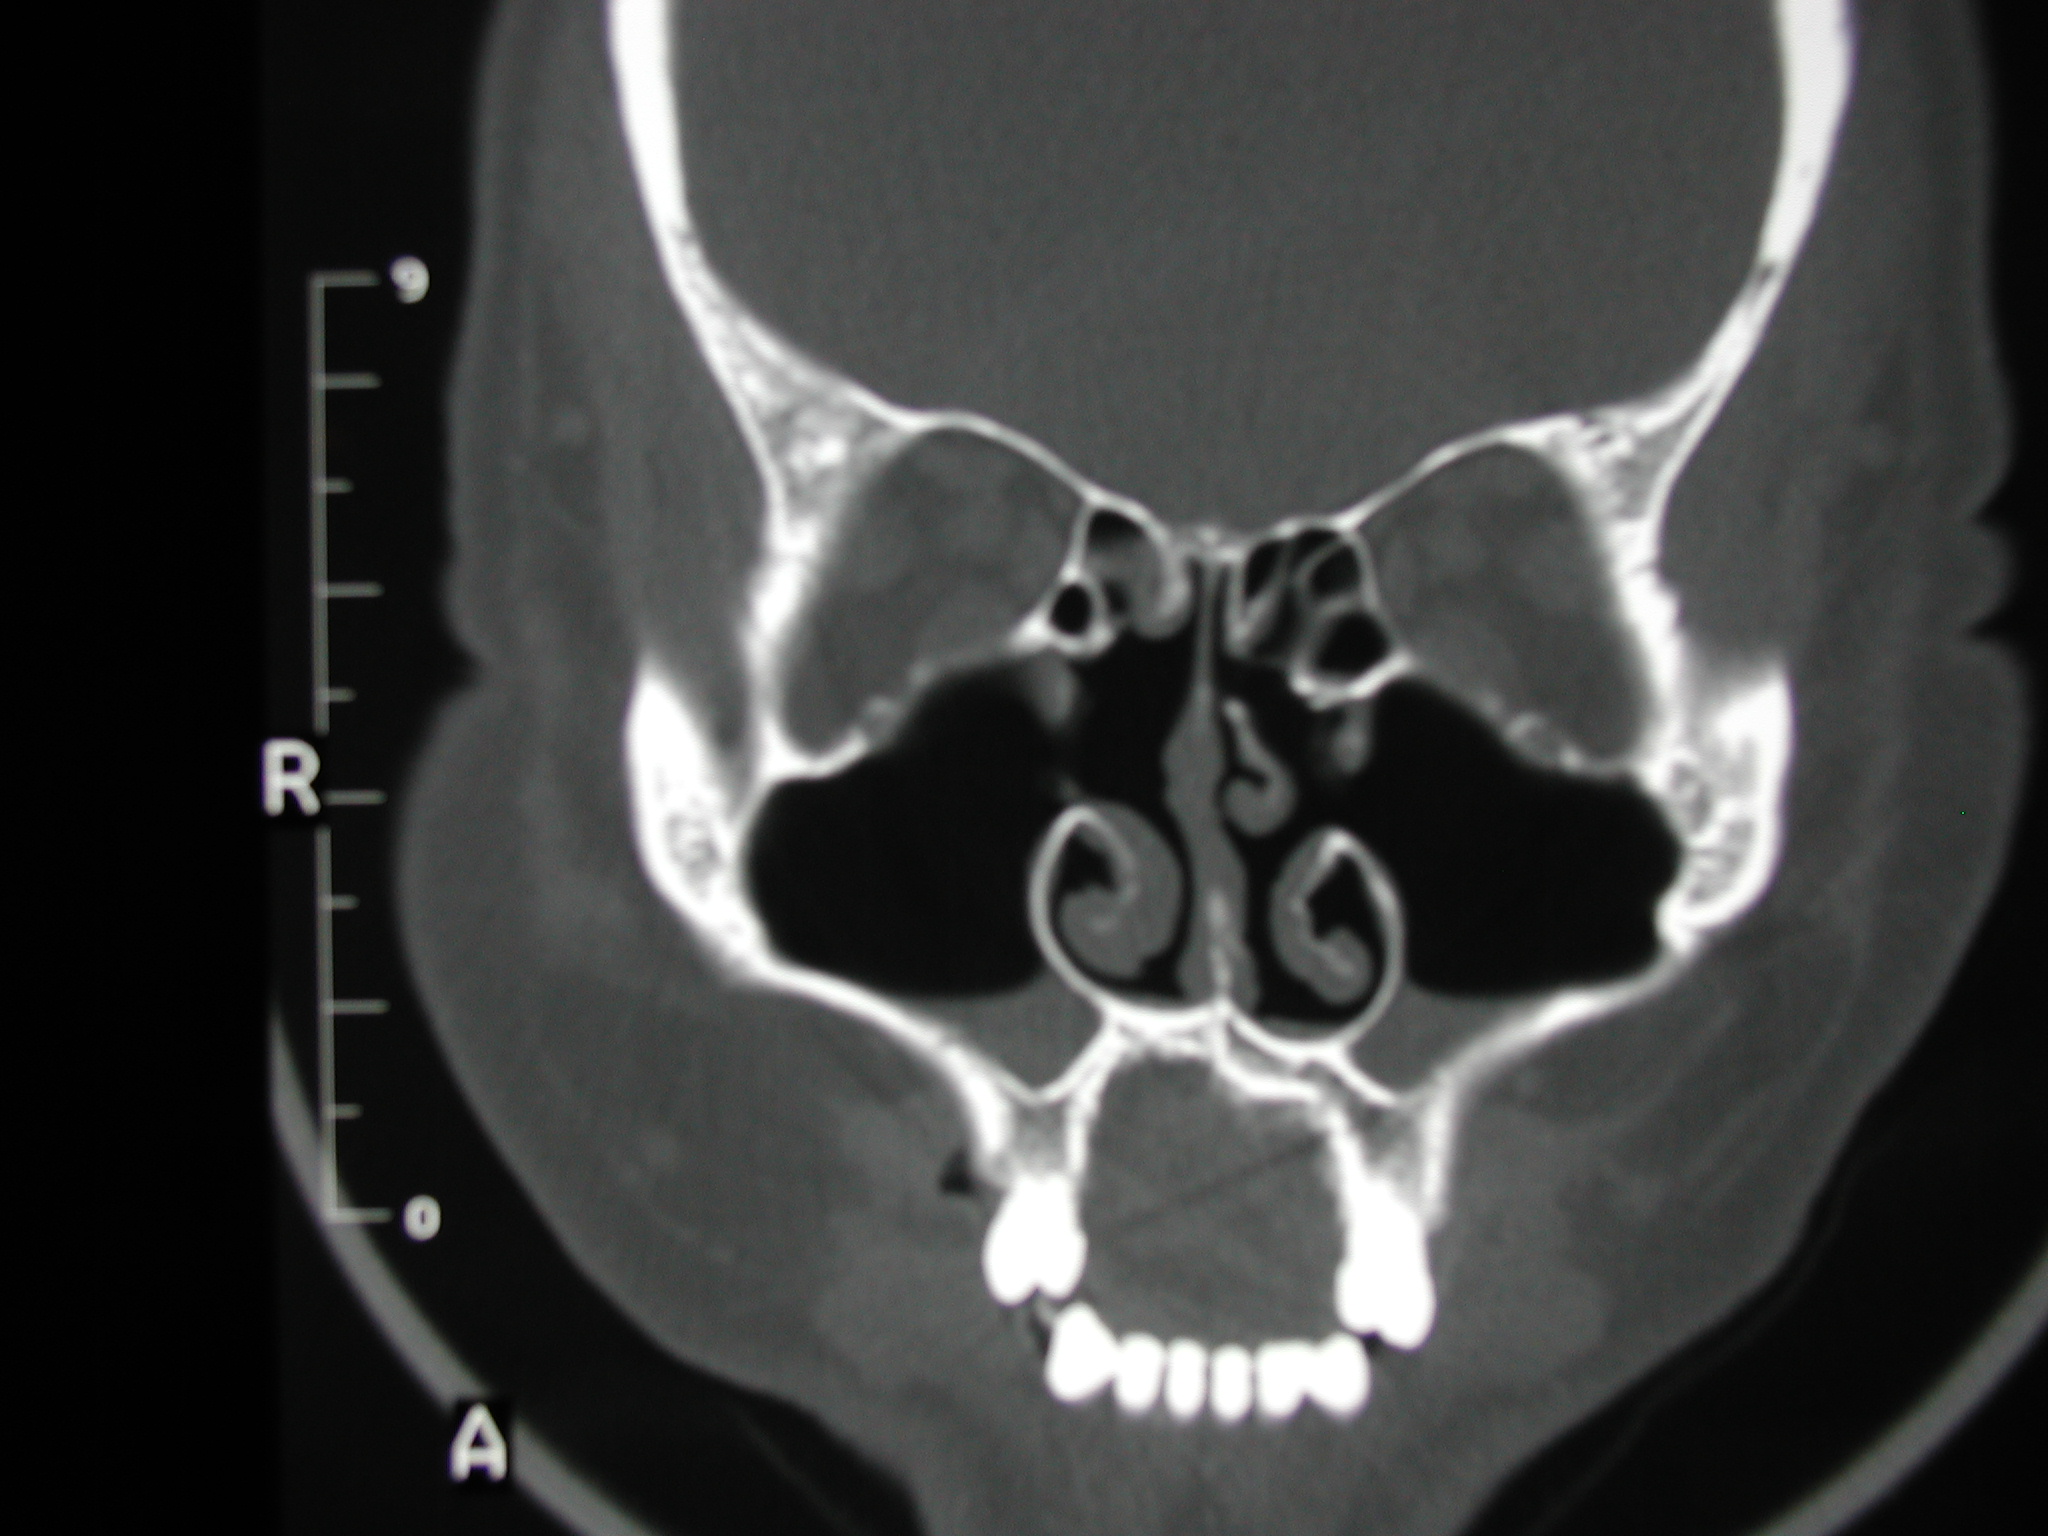

The patient above demonstrated clinical recirculation.  The intraoperative picture is located on another page.  The natural ostia are visualized in the first scan, and the large, though ineffective, iatrogenic ostia are seen in the second scan.